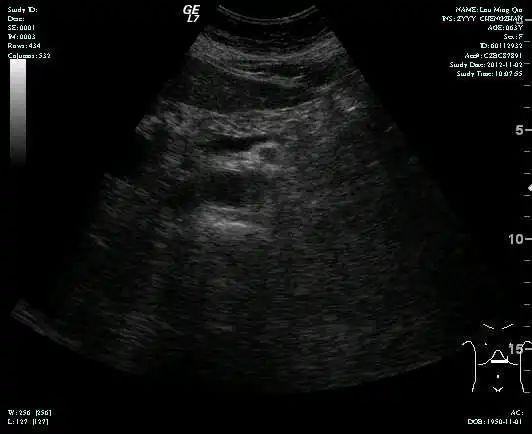

MR-H1

影像学检查结果评估:cPD。

疗效评估:cPR